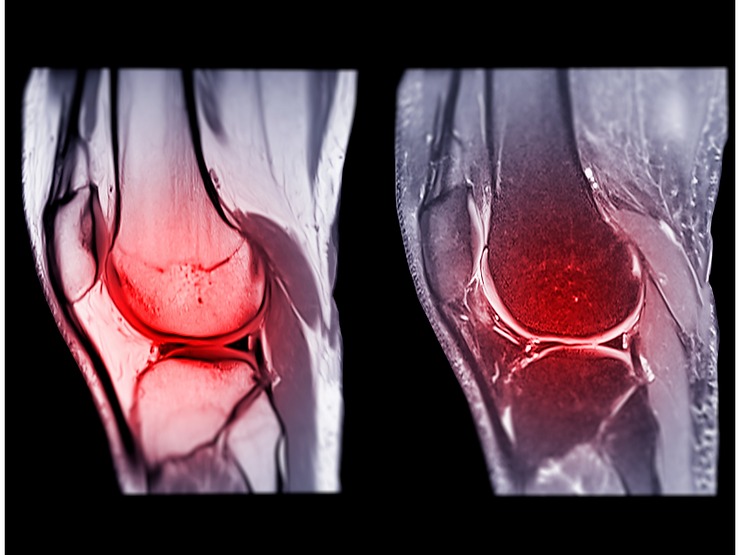

• Preparation: Before surgery, patients undergo a thorough evaluation, including physical exams and imaging (MRI or X-rays) to assess the extent of the ACL injury. Your surgeon will discuss graft options with you, considering factors such as age, activity level, and personal preferences.